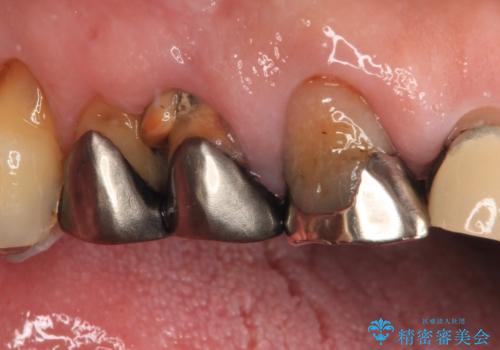

前歯のかぶせもののやり直し、根の治療も